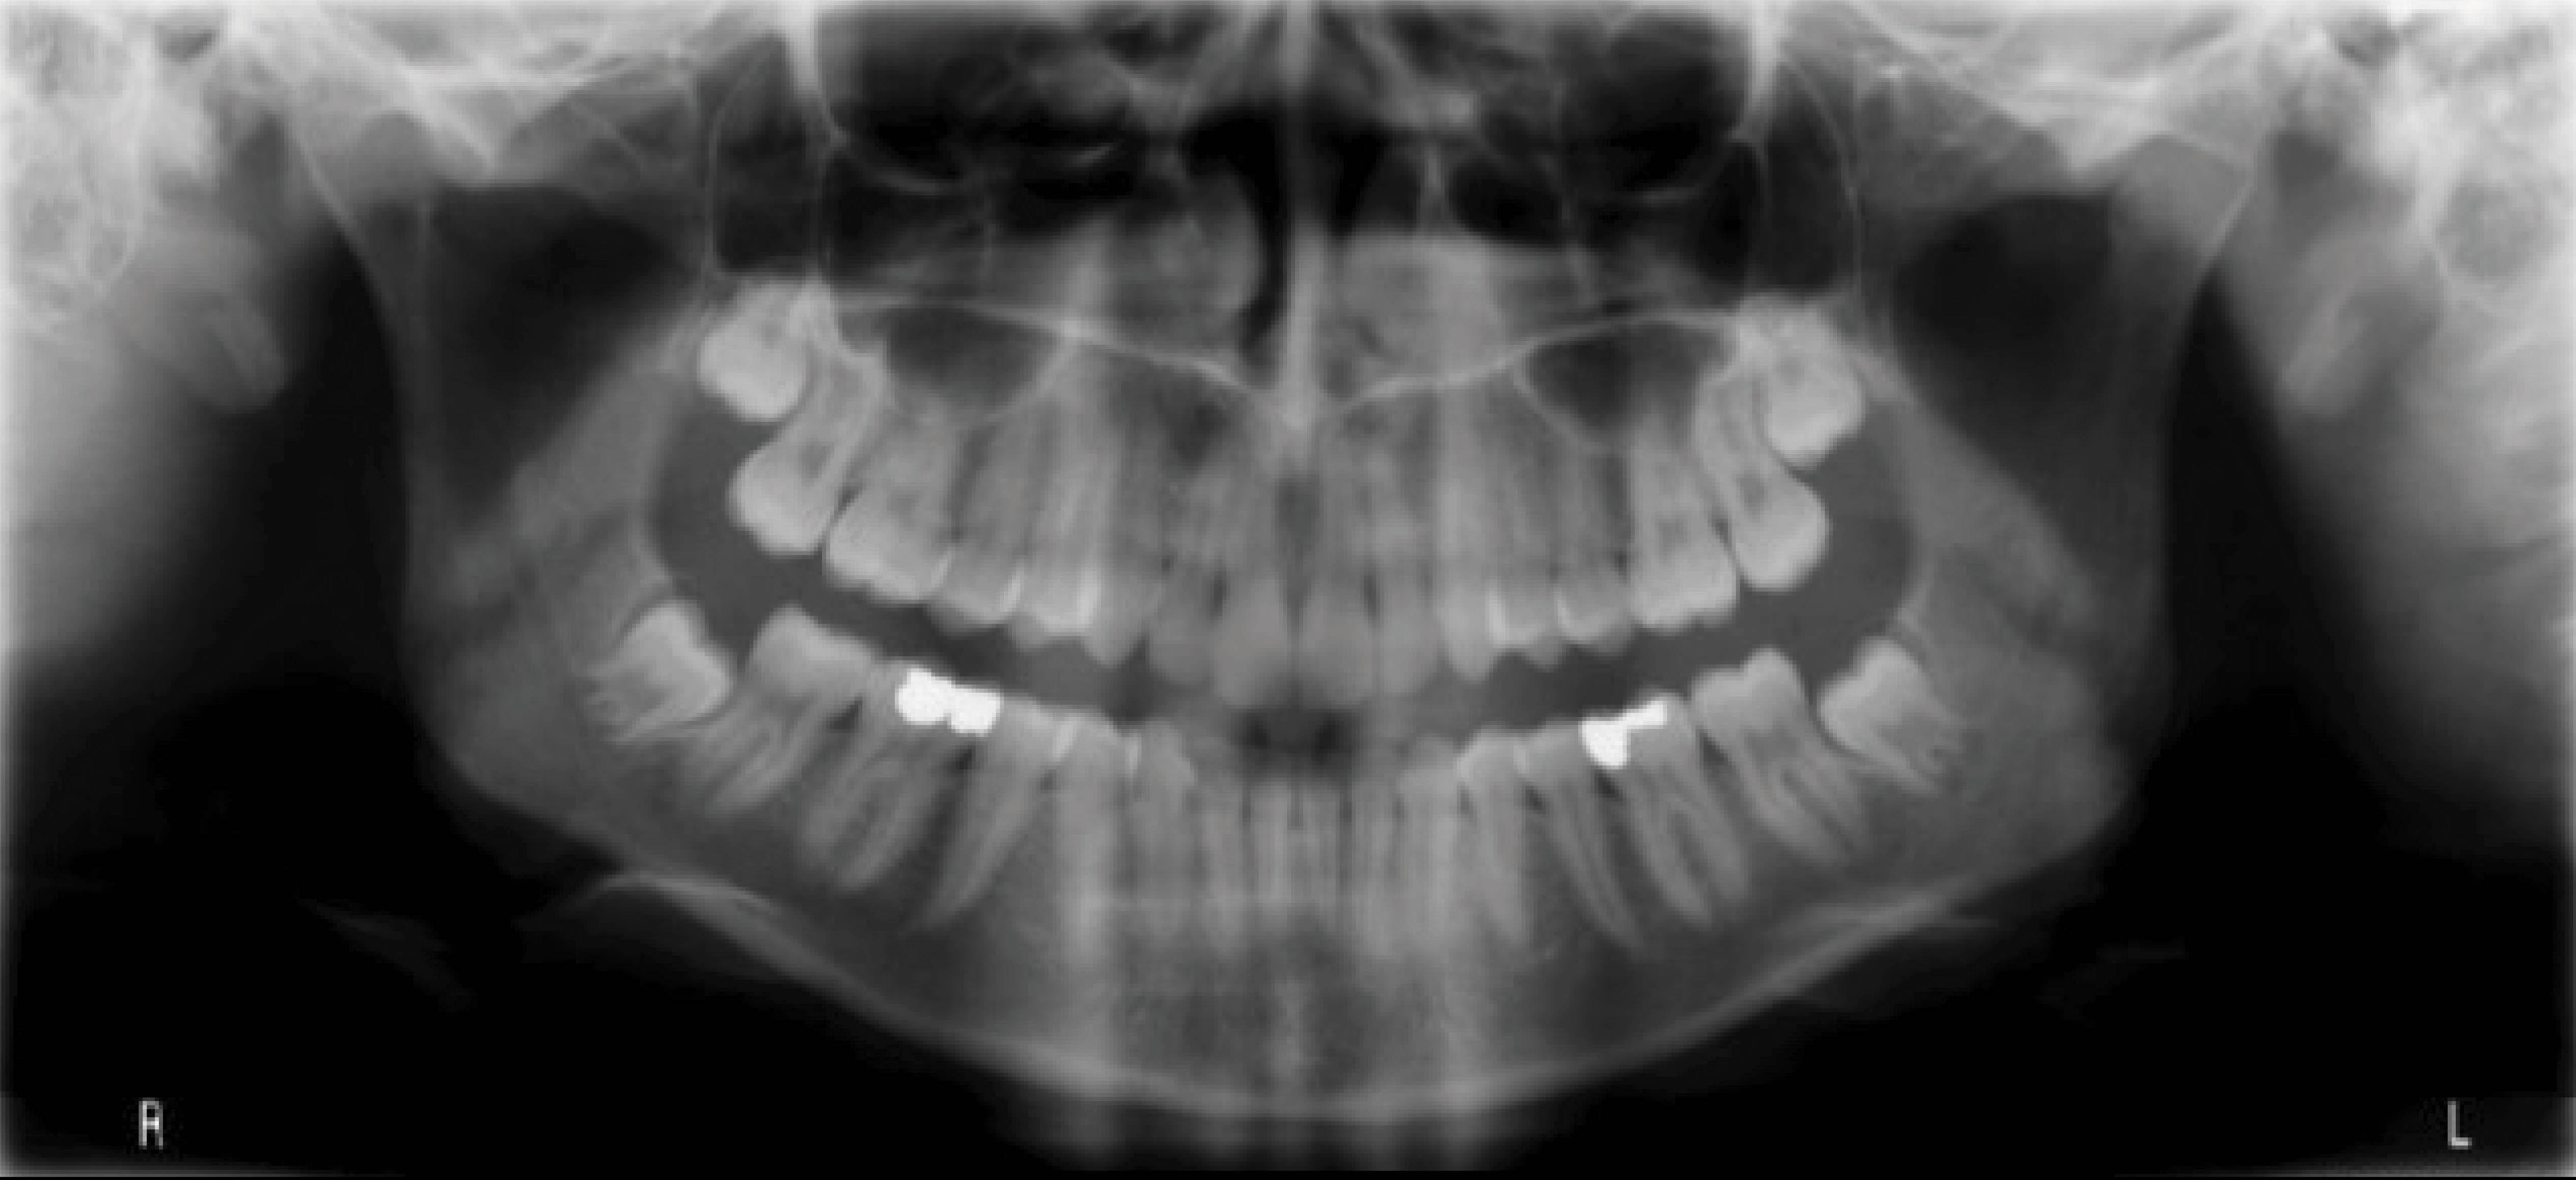

بیمار بعدی دختر ۱۲ ساله در مرحله اواخر میکس دنتیشن (شکلهای 92-۶ الی 94-۶) با اکلوژن ClII/1 است، دیپ بایت و کرادینگ دو فک دارد و لینگوالی شدن دندانهای قدامی بالا و پایین مشخص است. در (شکل 92-۶) هر دو لترال پایین را مشاهده میکنید که بلاک شدهاند. در OPG چیز خاصی مشاهده نمیشود و در لترال سفالومتری ارتفاع عمودی صورت کمی کاهش یافته و انسیزورها رترود شدهاند.

شکل 92-6

شکل 93-6

شکل 94-6

بخاطر در حال رشد بودن بیمار، استفاده از الاستیک کلاسII باعث اصلاح اکلوژن میشود. اصلاح کرادینگ با اکسپنشن خلف و پروترود نمودن قدام انجام میشود. اصلاح دیپ بایت به صورت نسبی و با پروترود شدن قدام انجام میگیرد.